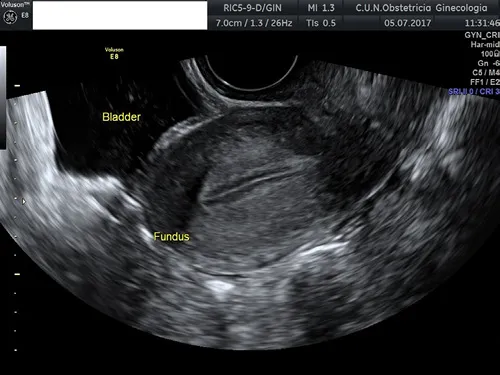

The bladder is easily identified as a central cystic structure located between the uterus and the abdominal wall (Figure 1.4). Bladder wall thickness can be measured, and the internal wall surface may be evaluated. It is a common finding to observe some irregularities of the bladder mucosa. When scanning an oncological patient, it is quite important to determine the presence of sliding of the bladder wall over the cervix, since this is a sign that indicates that the bladder wall is not involved, for example, in a case of cervical carcinoma.

Figure 1.4 Transvaginal ultrasound showing the uterus in the longitudinal plane. The bladder can be seen as an anechoic structure located anteriorly to the uterus.